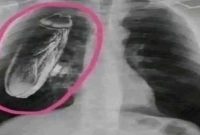

বিচিত্র জগৎ ডেস্ক : কেনিয়ার একটি সরকারি হাসপাতালে ঘটেছে চাঞ্চল্যকর ও বিব্রতকর একটি ঘটনা। এক রোগীর বুকের এক্স-রে করার পর চিকিৎসকরা তাকে জানান, তার বুকের ভেতরে নাকি একটি জীবন্ত তেলাপোকা রয়েছে। এমন অস্বাভাবিক ‘রিপোর্ট’ দেখে রোগীকে উন্নত চিকিৎসার জন্য সিঙ্গাপুরে যাওয়ার পরামর্শ দেওয়া হয়।

চিকিৎসকদের পরামর্শ অনুযায়ী রোগী সিঙ্গাপুরে যান। তবে সেখানে পৌঁছে এক্স-রে ও অন্যান্য পরীক্ষা-নিরীক্ষার পর ভিন্ন চিত্র সামনে আসে। সিঙ্গাপুরের চিকিৎসকরা জানান, রোগীর বুকের ভেতরে কোনো তেলাপোকা নেই। আসলে তেলাপোকাটি ছিল এক্স-রে মেশিনের ভেতরে আটকে থাকা, যা স্ক্যানে ভুলভাবে ধরা পড়েছিল।

পরবর্তীতে বিষয়টি স্পষ্ট হলে জানা যায়, এক্স-রে যন্ত্রের ভেতরে থাকা তেলাপোকাটিই ছবিতে এমনভাবে প্রতিফলিত হয়েছিল যে তা রোগীর শরীরের ভেতরে রয়েছে বলে মনে হয়েছিল। এই ভুল ব্যাখ্যার কারণেই রোগীকে অপ্রয়োজনে বিদেশে যাওয়ার পরামর্শ দেওয়া হয়।